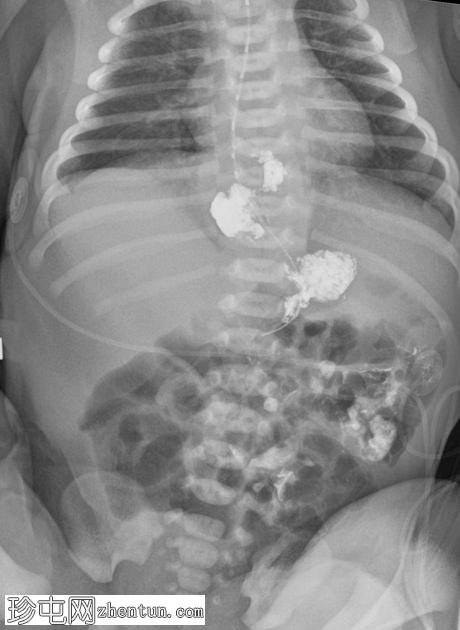

延迟1小时拍摄的X线片显示食管裂孔疝和胃部仍有造影剂残留,造影剂远端扩散受限,很可能是由于造影剂用量较少所致。充满气体的肠袢外观正常,乙状结肠内可见气体,直肠内未见气体。

这是一例儿童患者在透视下发现的食管裂孔疝病例。

最初的临床考虑是肠旋转不良,因为患者频繁且呕吐量大,但后来怀疑这是由中等大小的食管裂孔疝引起的。